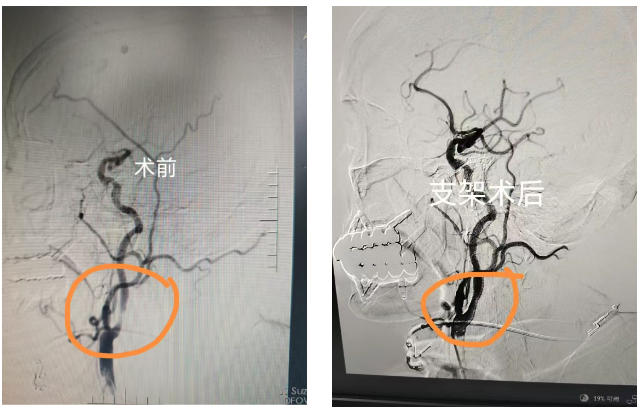

入院后患者病情突发进展,出现嗜睡、肢体偏瘫、失语、吞咽困难等症状,神经介入团队立即启动急症介入诊疗流程,在与家属充分沟通并获得同意后,紧急为患者施行右侧颈内动脉支架植入术,手术过程顺利,血管成功开通,术后患者症状改善,神志转清,肢体肌力明显好转。为从根源上解决多支血管狭窄问题,彻底消除脑梗复发隐患,待患者病情稳定后,神经介入团队再次精准施策,先后为患者完成左侧锁骨下动脉、右侧椎动脉开口处支架植入术,成功为患者重建脑部供血通路,术后患者的肢体、语言及吞咽功能逐步恢复,目前正在接受后续康复治疗。